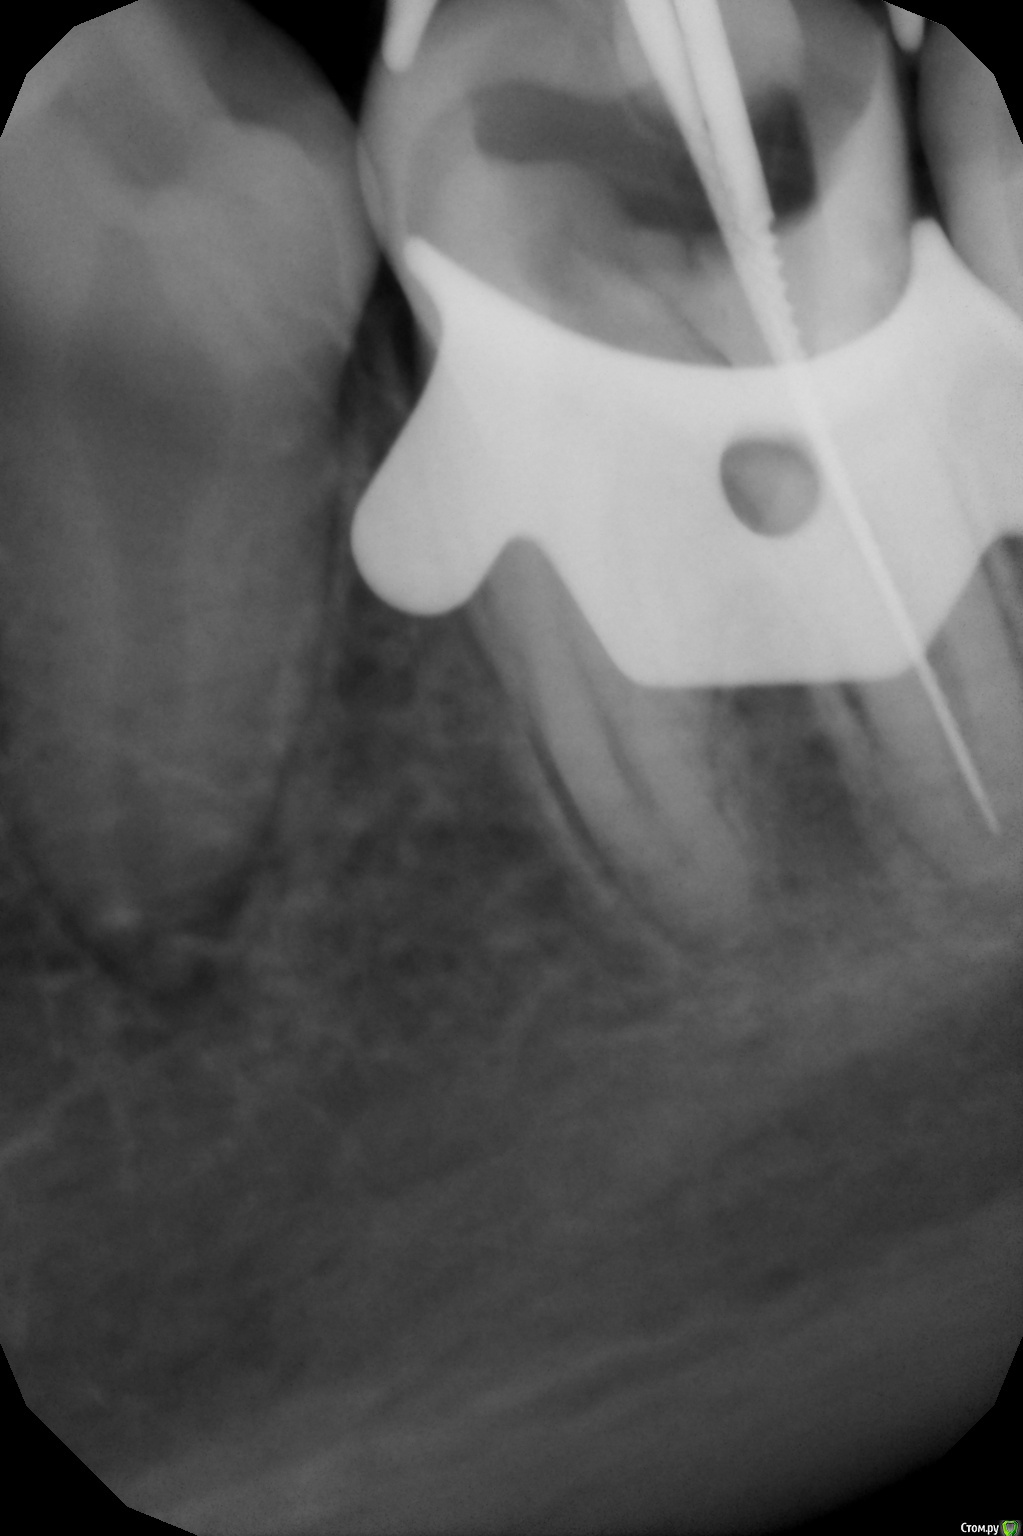

crown Опубликовано 7 апреля, 2016 Поделиться Опубликовано 7 апреля, 2016 Мне нужно минимум четыре. 1. Диагностический 2. С инструментом в дистальном и щечном. 3. С инструментом в язычном. 4 Контроль. Дитятко не засияет? Ссылка на комментарий

Stomart Опубликовано 7 апреля, 2016 Поделиться Опубликовано 7 апреля, 2016 А почему нельзя один с двумя инструментами? 1 Ссылка на комментарий

crown Опубликовано 7 апреля, 2016 Автор Поделиться Опубликовано 7 апреля, 2016 А почему нельзя один с двумя инструментами?так точнее, да и бывает наслаиваются сразу два Ссылка на комментарий

anvladd Опубликовано 7 апреля, 2016 Поделиться Опубликовано 7 апреля, 2016 так точнее, да и бывает наслаиваются сразу дваразные инструменты засунте. 3 Ссылка на комментарий

crown Опубликовано 8 апреля, 2016 Автор Поделиться Опубликовано 8 апреля, 2016 разные инструменты засунтену ок, а как быть с дистальным? разные файлы и разные размеры Ссылка на комментарий

ЕленаВалерьевна Опубликовано 8 апреля, 2016 Поделиться Опубликовано 8 апреля, 2016 (изменено) ну ок, а как быть с дистальным? разные файлы и разные размерыну так и пусть разные файлы и размеры, а если наслаивается попробуйте в другой проекции. Вы сами снимки делаете или м/с? Изменено 8 апреля, 2016 пользователем ЕленаВалерьевна Ссылка на комментарий

crown Опубликовано 8 апреля, 2016 Автор Поделиться Опубликовано 8 апреля, 2016 ну так и пусть разные файлы и размеры, а если наслаивается попробуйте в другой проекции. Вы сами снимки делаете или м/с?Я сам, м\с у нас к этому отношения не имеют, а рентгенолог фоткает только в одной проекции, как его учили. Тем не менее вопрос остается открытым. Ссылка на комментарий